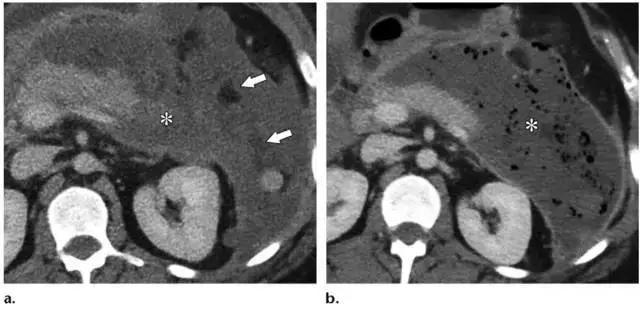

ANCs 发生于发病 4 周内的坏死性胰腺炎,其内含有坏死物,多见于小网膜囊和肾周,也可发生于胰腺实质内。他们可为多灶性,有分隔,可延伸至盆腔。

ANCs 也含有大量液体,和 APFCs 的鉴别是 ANCs 含有非液性成分,比如实性成分或脂滴。如果有碘对比剂禁忌证,平扫 CT 如果能发现脂性密度对确定坏死及诊断 ANCs 具有重要帮助(图 9)。

在胰腺炎早期,APFC 和 ANC 的鉴别比较困难。发病后 2 周的影像学检查对鉴别两者具有重要意义。所有与坏死胰腺实质相通的胰周异常病灶即使看不到非液性碎片也应诊断为 ANC。

图 10 48 岁坏死性胰腺炎女性患者 2 个月内的演变过程。a 1 周:轴位增强 CT 示胰颈坏死(*)。b 2 周:轴位增强 CT 示新发胰颈(*)坏死相连的胰周(箭头)坏死,征象符合 ANC。c 3 周:周围 T2WI MR 图像更清晰的显示了 ANC(*)的内容物,包括液性高信号和非液性坏死物,后者又包括胰颈和胰体的坏死(箭头)。注意局部壁形成。d 5 周:轴位增强 CT 示成熟壁形成,符合 WON(*)的诊断。e 囊肿胃引流术和清创术中内镜可见 WON 排出的坏死物(箭头)。f 7 周:术后增强轴位 CT 图像可见 WON 已成功清除,可见双尾支架影